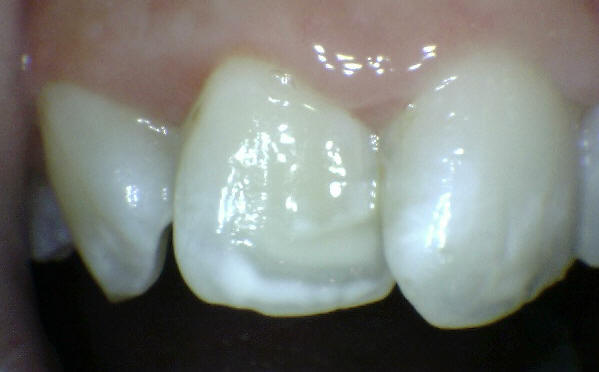

Una morfología de la fisura estrecha, con forma de botella de "Coca-Cola" genera un nicho ecológico ideal para la colonización de cualquier bacteria productora de ácidos. Al no poder remover en forma períodica dicho biofilm de una zona tan estrecha, el ataque ácido genera una lesión cariosa en la dentina, con un aspecto de esmalte intacto a la inspección visual, o sea un típico código 3 y 4 de ICDAS Completo. (Caries Moderada para el ICDAS COMBINADO)

Imagen digital que representa la microfiltración y penetración del sellante realizado.

Microfotografía: Muestra como el sellador obtura la caries subyascente, evitando su avance.

Código 3 (Caries moderada) in vitro. Los códigos 3 in vivo debe ser sellado para evitar el avance del proceso carioso. (MNO)

Código 4 (Caries moderada) in vitro. Los códigos 4 in vivo deben ser tratados en forma operatoria con preservación dental (MOPD), porque presentan dentina infectada.